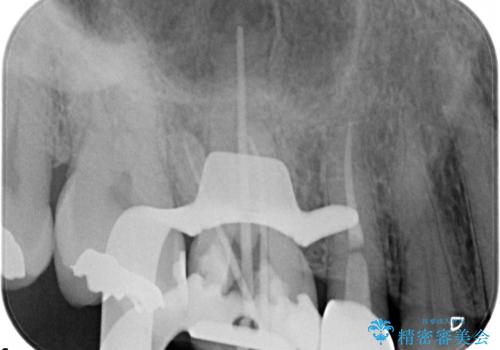

- 定期検診にて、奥歯の頬側歯肉にサイナストラクトが発見された患者様です。

根管治療から歯冠修復まで行っております。

サイナストラクト(瘻孔)から原因歯を特定し治療を行っております。根管治療を行った歯牙は破折リスクが高くなるため被せものによる治療を提案しております。